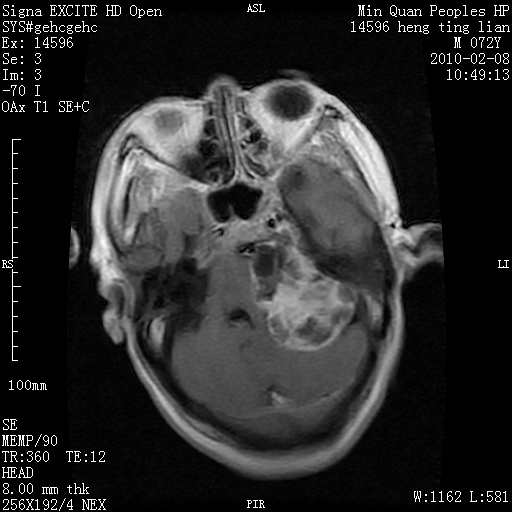

m,72,头疼,头晕两年,伴视力模糊三月,饮食呛咳两天。pe:颈部抵抗,左眼突出,左眼瞳孔约3mm,对光反射消失,双眼失明,伸舌困难,双肺呼吸音粗,心率110次/分,左上肢肌力i级,左下肢屈曲,肌张力高。现有08年2月19mri平扫及10年2月8日mri增强请会诊。ct病灶呈低密度伴散在点、片状等密度区,无明确钙化(无ct片资料可供上传)。[

脑外肿瘤,囊实性,环状不规则强化,内听道扩大,考虑神经源性肿瘤

左侧桥小脑区占位伴梗阻性脑积水----考虑 1神经鞘瘤 2室管膜瘤。

左侧桥小脑区神经鞘瘤伴梗阻性脑积水。

脑外肿瘤,病灶呈匍匐蔓延,表皮样囊肿可能性大。